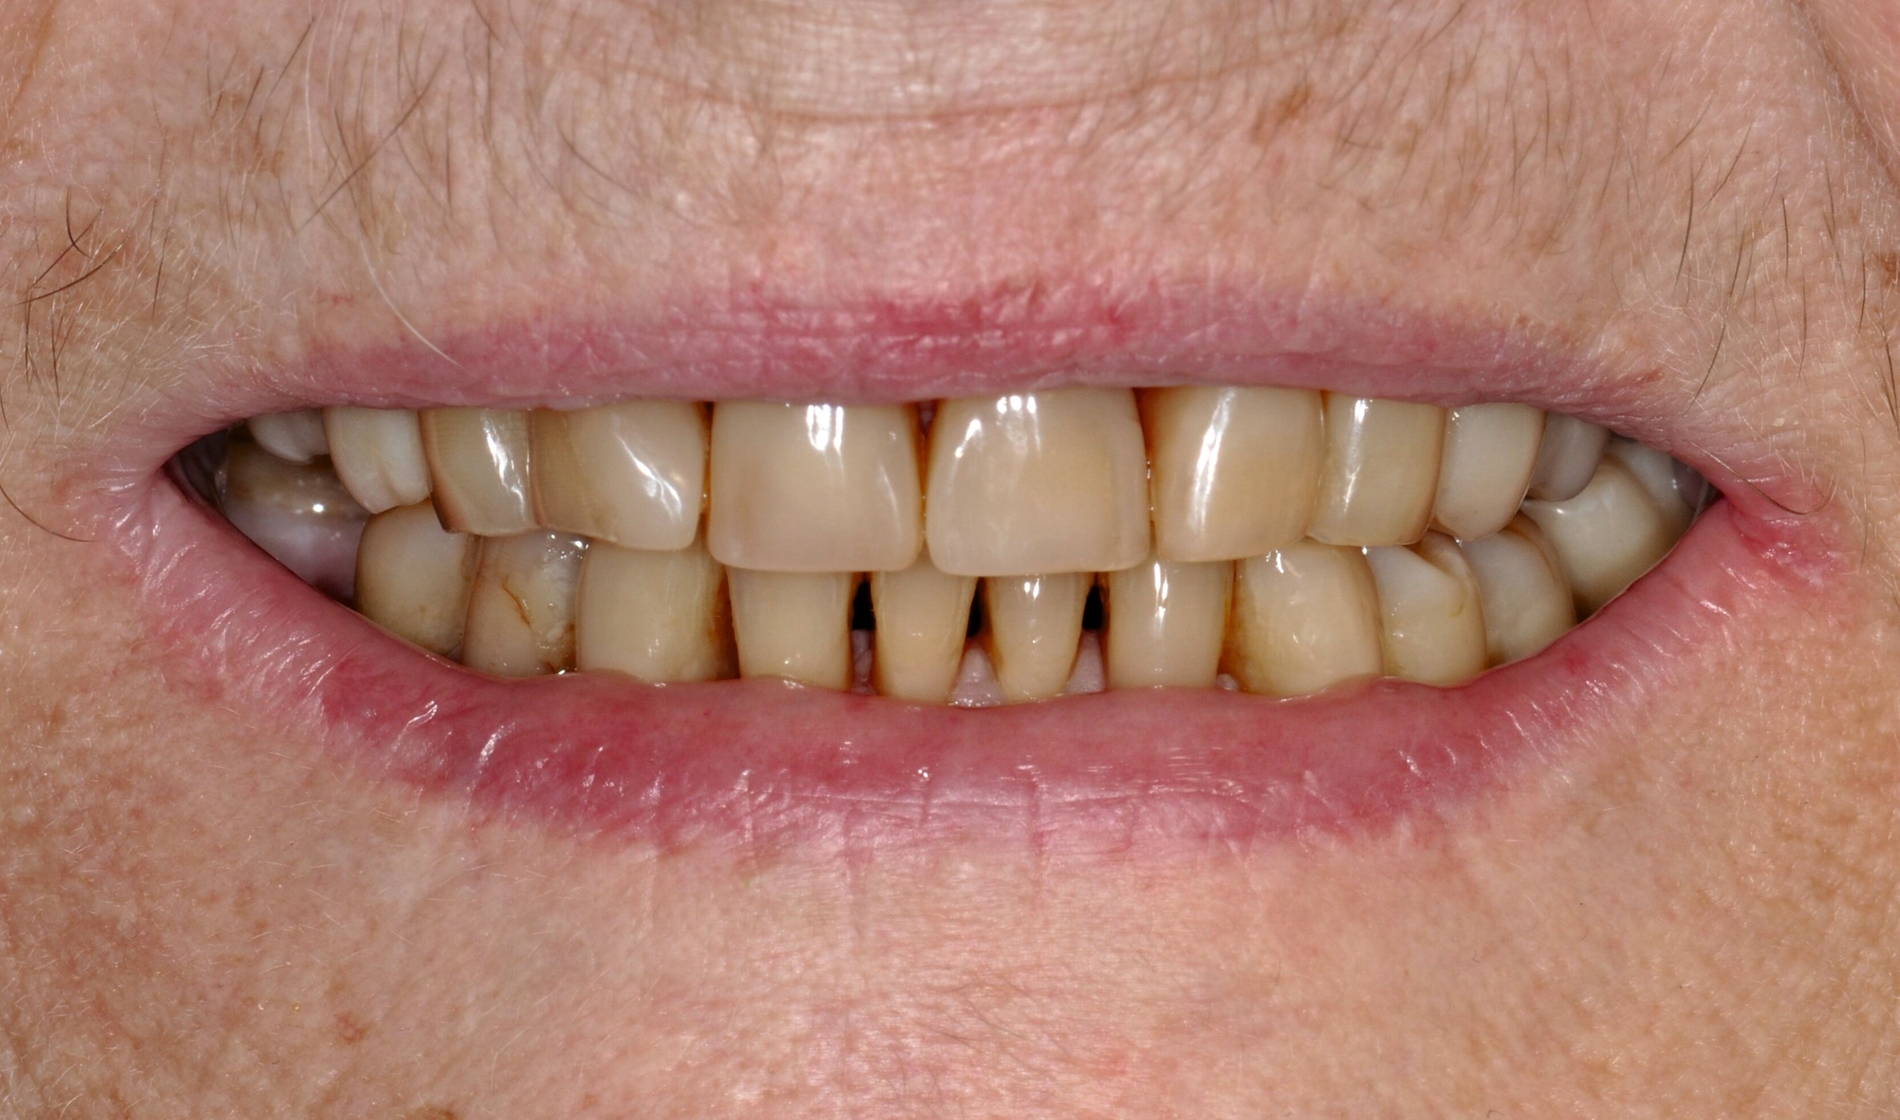

... für Zahnformkorrekturen im Frontzahnbereich

Ähnliche Ergebnisse wurden bei Zahnformkorrekturen erzielt. Die untersuchten Studien berichteten über hohe bis sehr hohe Überlebensraten von Komposit-Restaurationen mit Nachbeobachtungen bis zu 15 Jahren. Beim Vergleich mit indirekten Keramikveneers zeigten diese zwar höhere Überlebensraten, doch basiert diese Schlussfolgerung auf einer einzelnen Studie mit kurzer Nachbeobachtungszeit [Meijering et al., 1998]. Die Nutzen-Schaden-Bewertung spricht klar für den Einsatz von Kompositen zur Zahnformkorrektur im Frontzahnbereich (Abbildung 3), aufgrund der hohen Überlebensraten, der guten bis ausgezeichneten klinischen Qualität, der Reparierbarkeit und der geringeren Invasivität im Vergleich zu Keramikveneers. Der elektive Charakter dieser Verfahren sollte bei der Gesamtbeurteilung berücksichtigt werden. Für diese Behandlungen wird ein minimalinvasiver oder nichtinvasiver und präventionsorientierter Ansatz empfohlen.